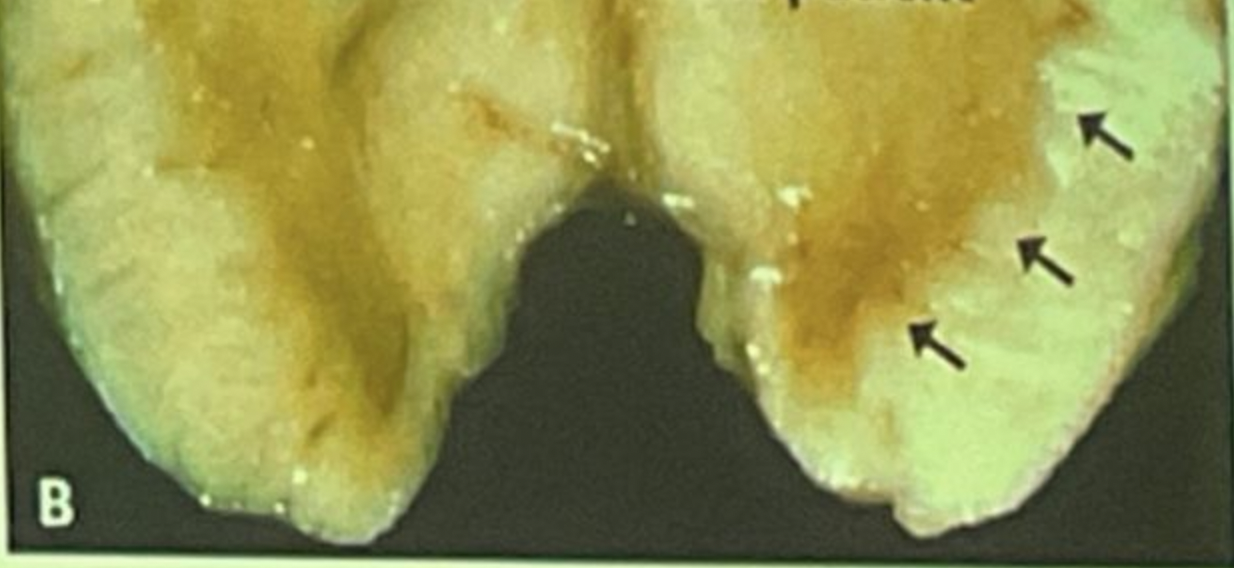

¿Que es esto?

Paciente con enfermedad de parkinson (cuerpos de lewy a la derecha)

Esta imagen se da en pacientes:

De manera más reciente se han descrito otras complicaciones más temidas con el uso de agonistas del receptor de dopamina, tales como: